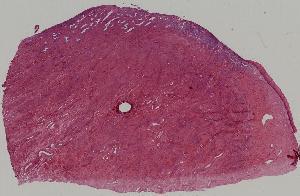

22.慢性宫颈炎